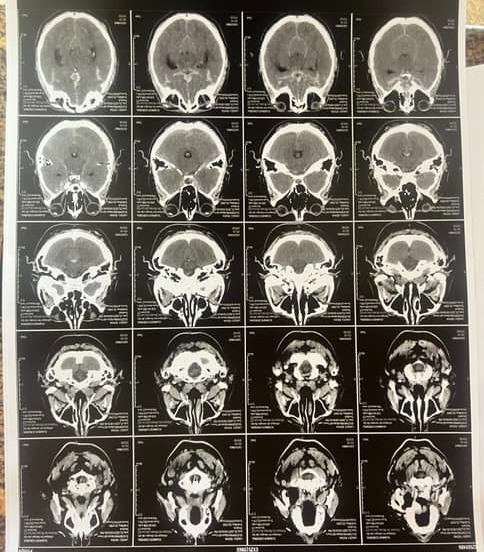

On July 23rd, our beloved father, Ridha, was found unconscious after hours of not responding. Earlier that day, he sounded confused — we thought he was just tired. But it was far worse: he had suffered a ruptured cerebral aneurysm, a life-threatening condition that needed immediate surgery.

At the first hospital, doctors misdiagnosed him and gave him aspirin, worsening the bleeding in his brain. By the time we got to a second hospital, precious hours had been lost. The public system couldn’t help — most neurosurgeons were away, and the one available wasn’t specialized. Our only option was a private clinic, but they refused to admit him to ICU without advance payment. Even after raising 20,000 dinars, they still said no — until public pressure and media involvement forced them to accept him.

On July 24th, Ridha finally underwent emergency brain surgery. He’s now in the ICU — stable, but still in critical condition. He’s uninsured, and each day in intensive care is pushing us further into debt, we're looking at 70,000 up until today.